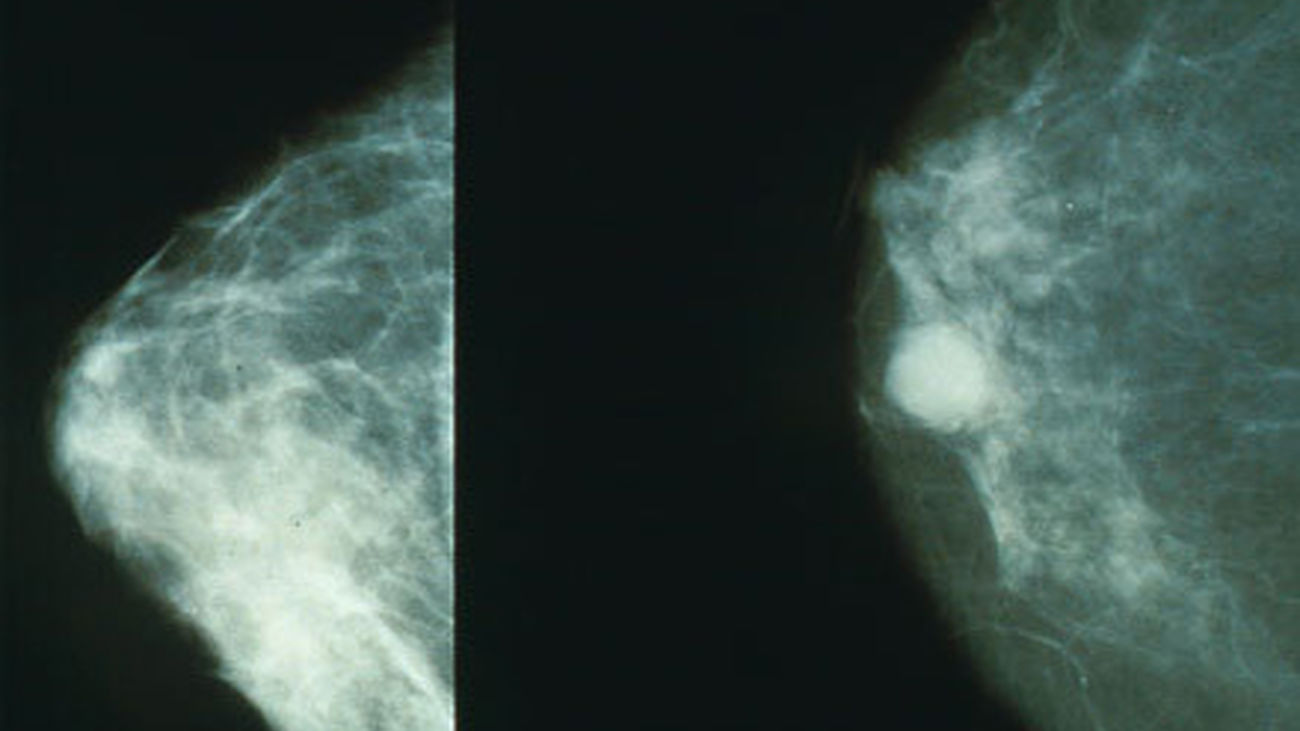

cancer_mamografia

cancer_mamografia |Archivo